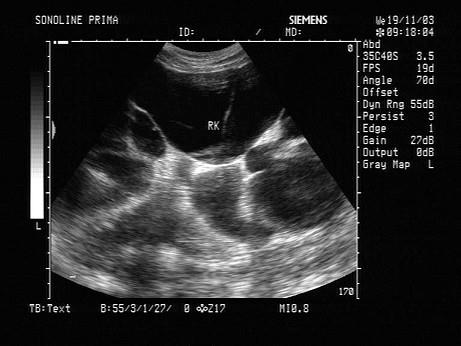

根据超声图像所示,该病例为哪型肾积水?(?)A.菱角型B.烟斗型C.花朵型D.调色板型E.巨大囊肿型

问题 根据超声图像所示,该病例为哪型肾积水?(?)

选项 A.菱角型 B.烟斗型 C.花朵型 D.调色板型 E.巨大囊肿型

答案 D